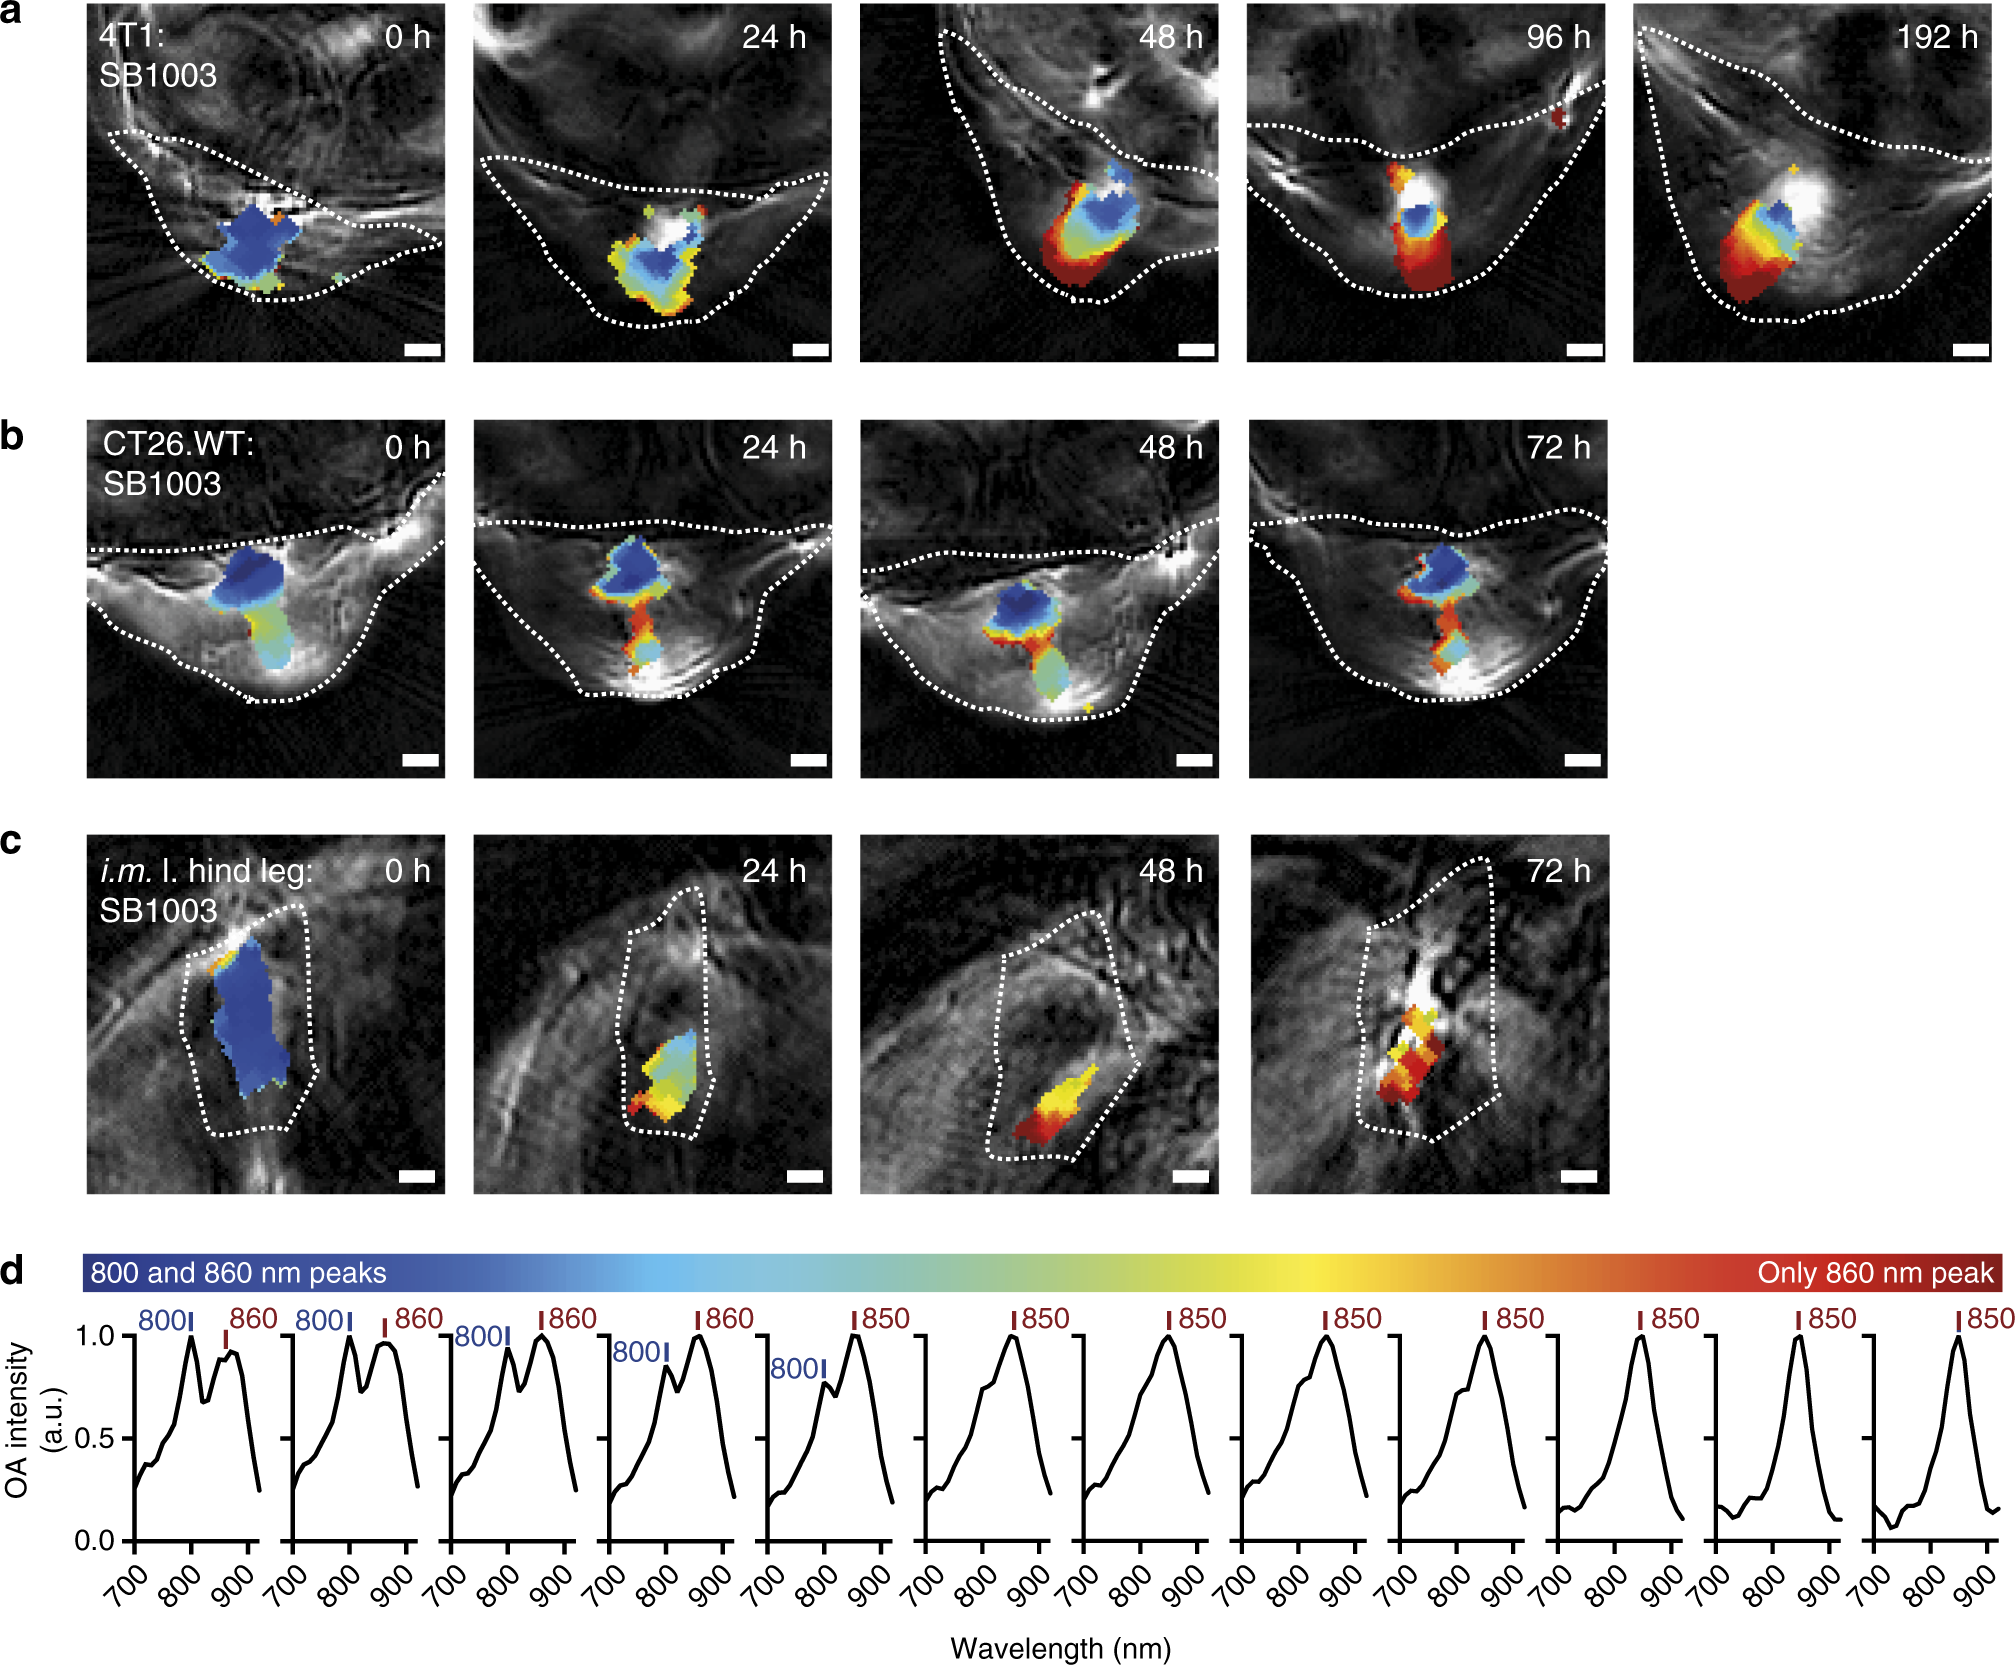

Fig. 3

From: Phototrophic purple bacteria as optoacoustic in vivo reporters of macrophage activity

Spatiotemporal change of the bacterial spectral signature in the tumor environment and the muscle. A 4T1 (a) and a CT26.WT (b) tumor-bearing mouse intratumorally injected with Rba. capsulatus SB1003 is shown together with the hind leg muscle with the same injection (c). Shown are representative reconstructed images overlaid by unmixed pixels in false colors. Color coded regions indicate a mixture of 800 nm/860 nm peaks or predominance of the 860-nm peak as visualized in d. Shown are mean spectra of all regions of the same color. Unmixed pixels are shown as black if automatic peak assignment failed. Strong signal (white) in the reconstructed images at 720 nm relates to high absorption by blood or other absorber that has not been identified by the unmixing procedure. Data for all mice at all timepoints can be found in Supplementary Figure 14 (a n = 3, b n = 3, c n = 2). The analyzed region of interest (i.e., tumor) is indicated as a dotted line. All scale bars, 1 mm